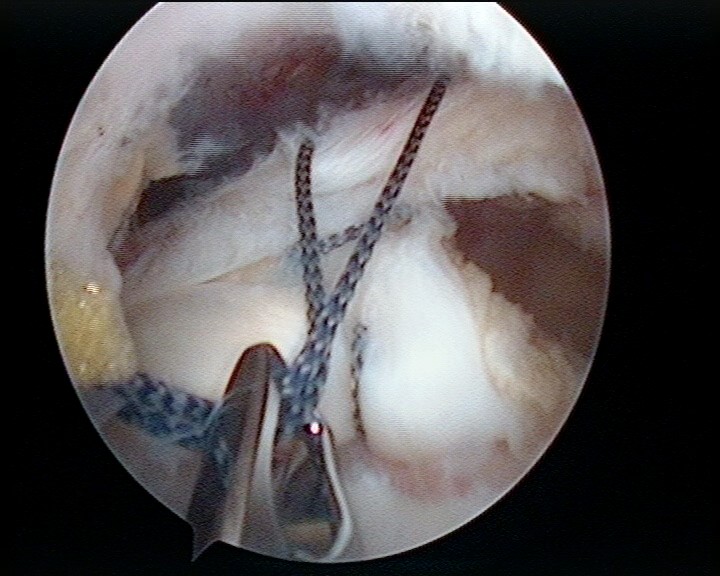

Eine innovative und schonende Operationsmethode bei schmerzhaften Schultern, die nur in wenigen Kliniken praktiziert wird, ist jetzt auch an der Orthopädischen Universitätsklinik Heidelberg etabliert worden. Dabei wird die eingerissene Muskel- und Sehnenmanschette des Schultergelenks schonend durch einen "Schlüsselloch-Zugang" genäht; die Patienten können ihren Oberarm wieder sicher und schmerzfrei ohne Einschränkungen bewegen.

Bei der bislang üblichen und bewährten Operationsmethode werden Haut und Mus-kel durchtrennt, um zu der gerissenen Sehne zu gelangen und diese zu vernähen. Die Langzeitergebnisse sind gut und reproduzierbar. Es besteht jedoch die Möglichkeit, die Sehnen der Rotatorenmanschetten auch endoskopisch/arthroskopisch zu nähen. Mittel- und langfristige Ergebnisse dieser Verfahren zeigen, dass die klinischen Ergebnisse vergleichbar dem traditionellen Verfahren, die Beweglichkeit aber besser und die Schmerzen nach der Operation geringer sind.

Dr. Laurent Lafosse und seine beiden Partner, Dr. Bruno Toussaint und Dr. Jerome Bahuel, gehören mit jährlich 2500 Operationen am Arm in Annecy weltweit zu den Koryphäen auf diesem Gebiet. Einen großen Anteil machen mit ca. 500 Operationen arthroskopische Rotatorenmanschettennähte aus. In Heidelberg konnten mittlerweile zahlreiche Patienten mit dem neuen Verfahren erfolgreich behandelt werden.